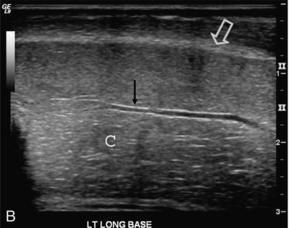

Penis birbirine paralel üç ayrı tüp şeklindeki yapıdan oluşmaktadır. Bu yapılardan altta olanı içerisinden idrar kanalı, damar ve sinir yapıları geçmektedir. Üstte olan iki tüp yapısı içerisinde ise etrafında kas tabakaları olan ufak havuzcuklar bulunmaktadır. Bu kas tabakaları normalde kasılmış bir durumda olurlar. Ereksiyon oluşumunu asıl sağlayan bu yapılara kavernöz cisim adını vermekteyiz.

Penil doppler ultrason incelemsei yaklaşık 30 dk süren bir testtir. Öncelikle ultrason ile penis yapıları ve damarlar değerlendirilir. Daha sonra ereksiyon sağlayıcı ilaçların olduğu bir enjeksiyon yapılır. Bu enjeksiyon ağrılı bir işlem değildir. Daha sonra bir süre beklendikten sonra 5’er dakika aralıklarla atardamar ve toplardamar hızları ve debileri ölçülür. 20.dakika ölçümüde yapıldıktan sonra işlem sonlandırılır. Bütün işlem parametrelerinin olduğu ayrıntılı bir rapor yazılır ve üroloji uzmanının doğru tedavi yöntemini tercih etmesini yolu sağlanır. Bu testte önemli olan hastanın sakin, kalabalık olmayan, gürültünün olmadığı bir ortamda bu işlemi yapmak ve bu test için yeterli zamanı ayırmaktır. Hastane ortamlarındaki kalabalık ve gürültülü alanlarda bu testi yapmak doğru sonuçların alınmamasına yol açacaktır.